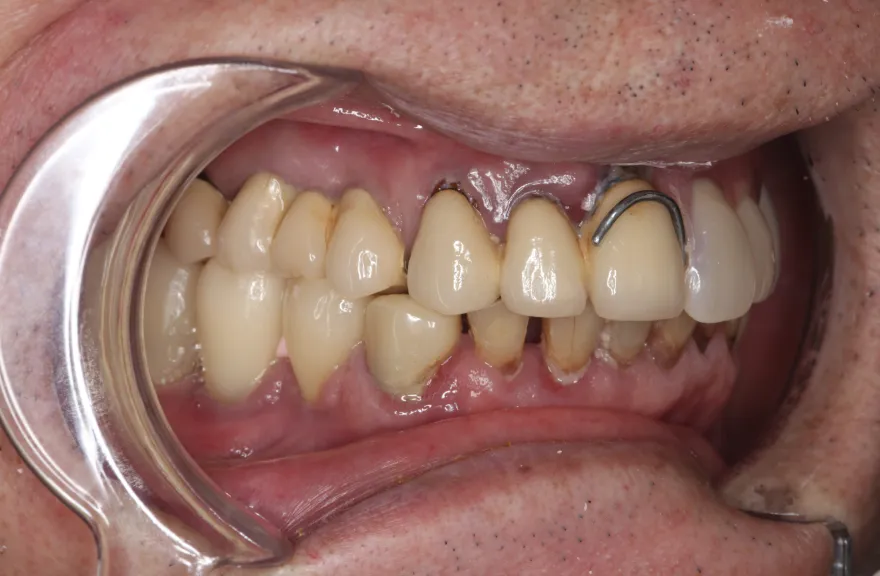

【治療例 5】上の歯がグラグラで困っている 62歳

- 数年前に全体的に治療したが、上のつながっている歯がグラグラして噛めないということで来院されました。

上顎は5本の歯を保険のブリッジ治療で連結してある状態でした。どの歯の状態も良くなく、今回なんとか治療を行ったとしても近いうちに再びトラブルを起こしてくることが予想されました。

下顎は9本の歯が残っており、虫歯はあるものの差し歯として使える状況でした。

しかし、患者さんとの話し合いの中で、「数年前に行った治療なのに再び全てやりかえないといけないのは単純にしんどい。もうやりかえのないようにしたい」という患者さんの強い思いが伝わってきました。

今回で完全に治療をやり切ってしまい、今後は最小限の介入で歯科と付き合えるよう、上下顎残っている歯の全ての抜歯、必要な本数のインプラント埋入、上顎は総義歯形態で対応することとしました。 - 治療のリスク